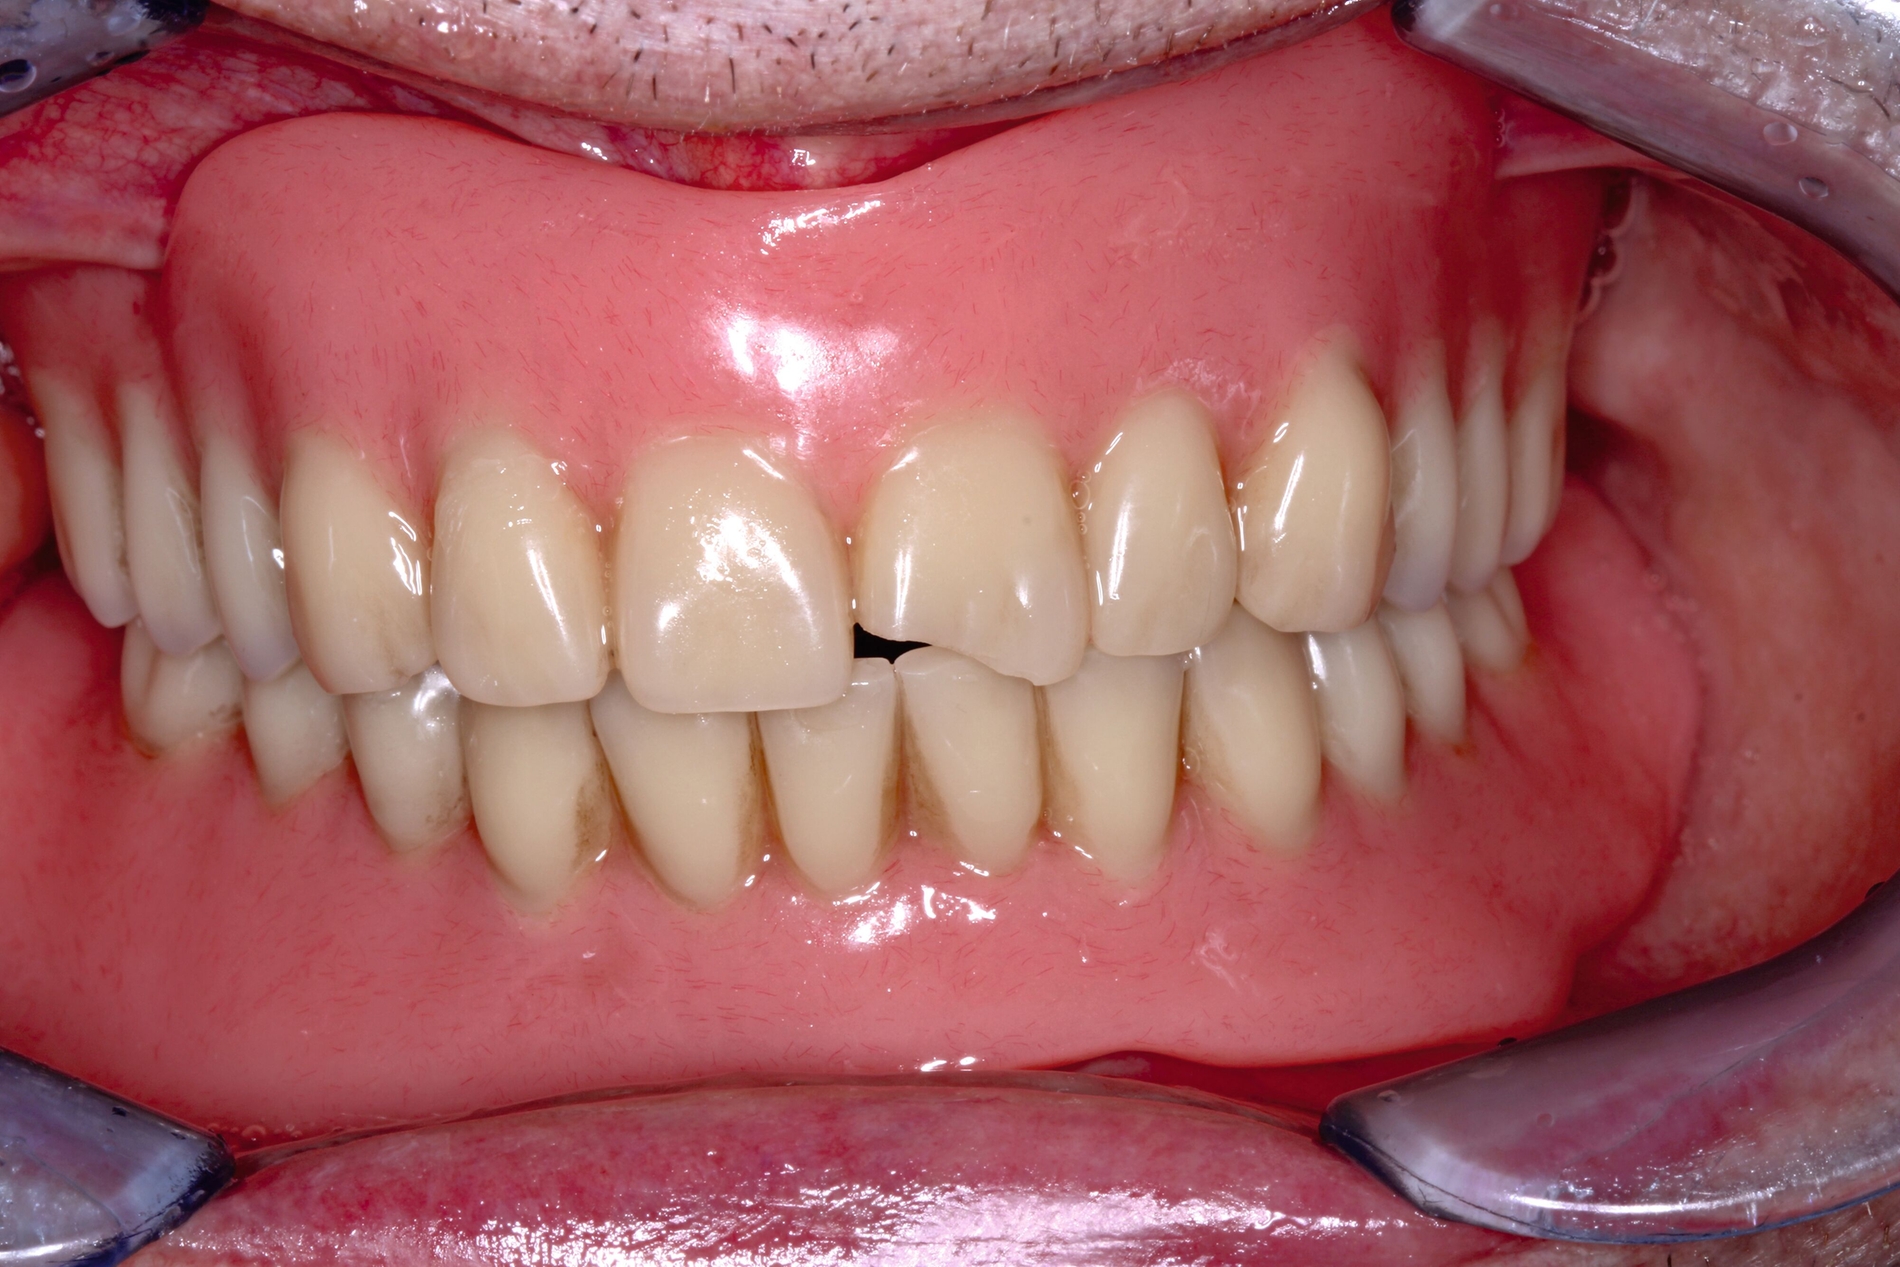

Patientinnen und Patienten mit stark reduzierter Therapiefähigkeit profitieren in besonderem Maß von zeiteffektiven Methoden und Materialien, zum Beispiel Bulk-fill-Kompositen, Reparaturfüllungen, Glasionomerzementen oder Intraoralscans. Die Therapiefähigkeit kann – ähnlich wie in der Kinderzahnmedizin – durch ein vertrauensvolles Verhältnis optimiert werden. Anders als in der Kinderzahnmedizin gibt es in der Alterszahnmedizin aber keine altersassoziierten Kontraindikationen für zahnmedizinische Interventionen. Voraussagbare Therapieergebnisse sind von besonderer Bedeutung, um erneute Behandlungen zu vermeiden. Das gesamte Spektrum zahnmedizinischer Interventionen kann bei der Behandlung von Personen mit Pflegebedarf sinnvoll sein. Die Abbildungen 6 bis 9 zeigen zahnmedizinische Interventionen bei Personen mit ausgeprägter Frailty (Stufe 7 der klinischen Frailty-Skala).